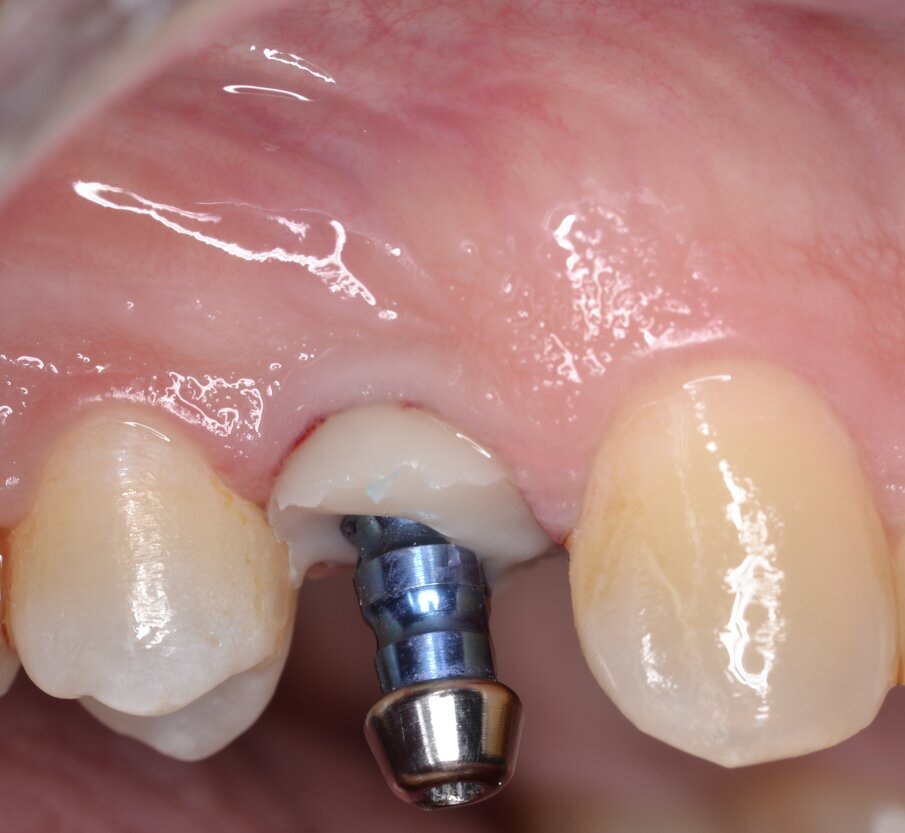

Viene inserito un impianto di tipo “bone level” da 3,5 x 15 mm: il raggiungimento di un torque di inserimento implantare (IT) superiore a 55 N.cm pone l’indicazione ad una procedura di provvisorizzazione immediata, motivo per cui un temporary abutment con una connessione protesica di tipo “platform switching” viene avvitato all’impianto con un torque di 35 N.cm (Figg. 10, 11). Per contrastare l’inevitabile contrazione dell’alveolo postestrattivo, il gap peri-implantare viene innestato con un biomateriale di origine eterologa (Figg. 12, 13). L’innesto viene eseguito con un leggero overbuilding in senso verticale allo scopo di sostenere il margine gengivale (Fig. 14).

Dopo aver protetto il sito chirurgico mediante un frammento di diga sterile (Fig. 15) una corona provvisoria in resina viene adeguatamente ribasata sul temporary abutment avvitato all’impianto, avendo cura di evitare qualsiasi tipo di contatto sia in occlusione centrica che durante i movimenti di lateralità e protrusione (Figg. 16, 17). Prima di dimettere il paziente con la corona provvisoria in situ, viene eseguito un esame radiografico endorale di controllo: trattandosi di un impianto “bone level” è consigliabile inserirne la piattaforma implantare circa 0,5 - 1 mm apicalmente alla cresta ossea marginale (Fig. 18).

Fig. 10 - Impianto inserito in posizione protesicamente corretta (IT > 55N.cm).

Fig. 11 - Moncone provvisorio serrato a 35 N.cm.

Fig. 16 - Corona provvisoria in resina ribasata sul moncone provvisorio (visione buccale).

Fig. 18 - Esame radiografico endorale di controllo.